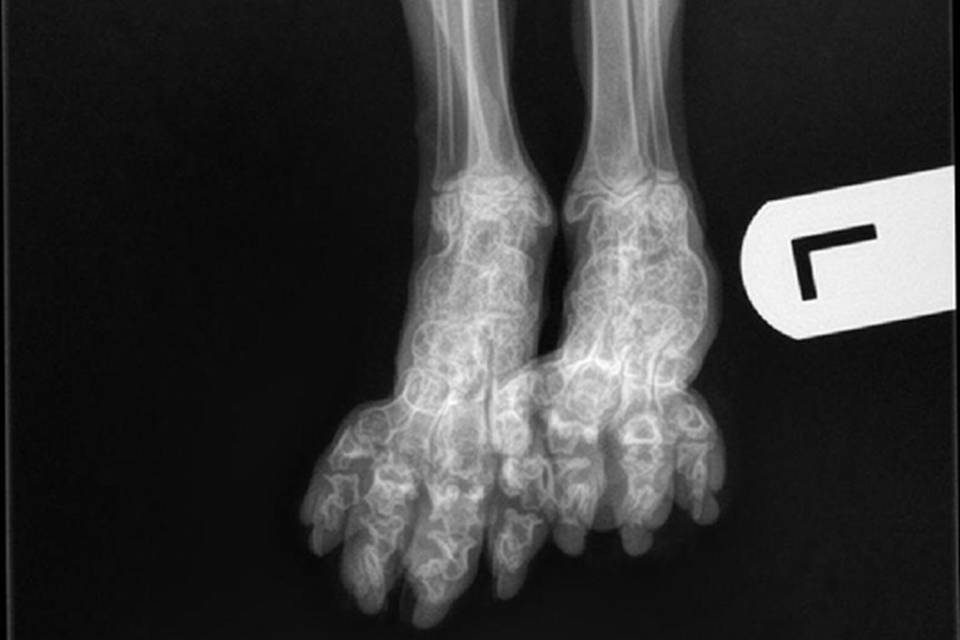

SFO is een erfelijke aandoening die voorkomt bij de Scottish Fold. Door deze afwijking zal het kraakbeen niet normaal volgroeien en functioneren. Hierdoor ontstaat ernstige artrose. Dit kan al op jonge leeftijd zichtbaar zijn en leidt ertoe dat aangetaste dieren mank en stijf gaan lopen en minder of niet willen springen.

De diagnose kan bevestigd worden door het maken van röntgenfoto's.